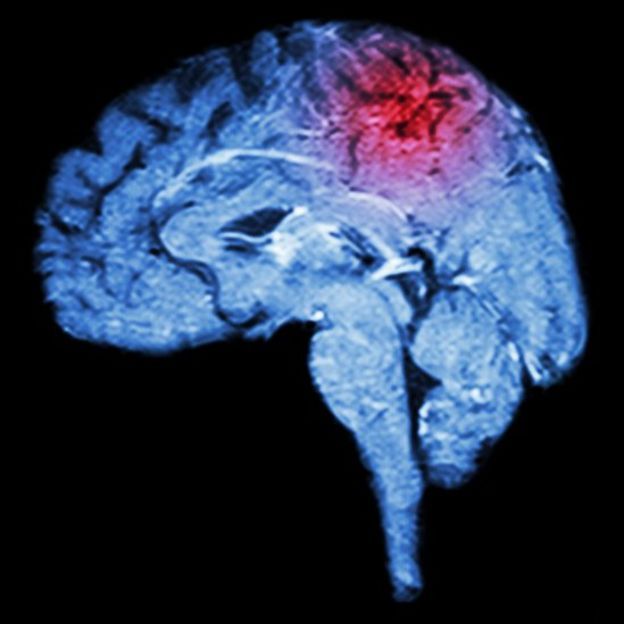

¿Qué son los miniderrames cerebrales y cómo nos damos cuenta de ellos?

Para miles de personas, se trató del preludio de que en pocos meses sufrirían un derrame cerebral. Los síntomas son similares, pero menos intensos y duran poco tiempo: incluso es cuestión de unos minutos.

Se les llama accidentes isquémicos transitorios (AIT) y para muchos es una advertencia infalible.

De acuerdo con Harvard Health Publications, revista de la escuela de Medicina de la Universidad de Harvard, padecer un miniderrame cerebral ha sido asociado con 12% a 20% de riesgo de tener un derrame cerebral en los siguientes tres meses.

"Cerca de 33% de las personas que han experimentado un AIT sufren de un derrame cerebral en el transcurso de un año", indica la publicación especializada.